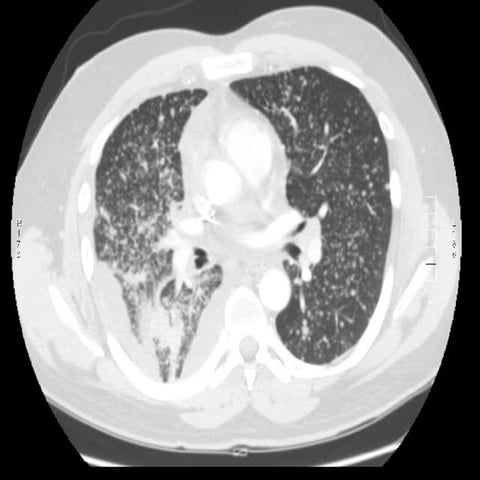

40 year old